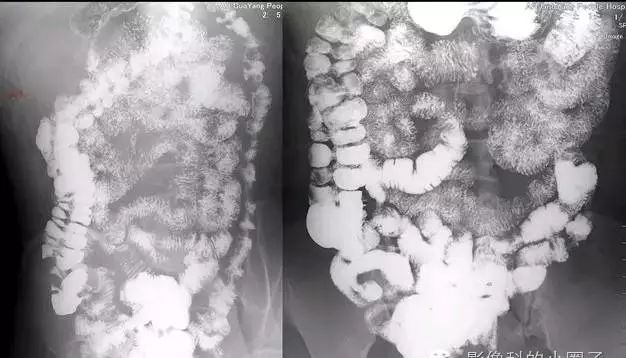

1.十二指肠

2.近段空肠

3.远段空肠

4.近段回肠

5.远段回肠

6.中段回肠